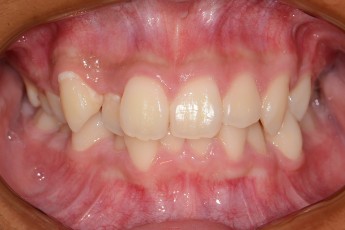

Before

After